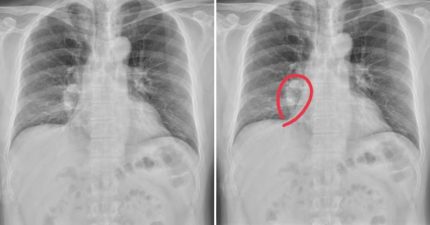

才咳嗽一個月「X光照出肺癌末期」 40歲男崩潰不信…日常1習慣洩端倪

April 18, 2023

台灣, 知識